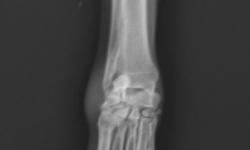

Pacient č.: 2. - rtg před operaci, hypertenze karpu.

Pacient č. 2.

• Plemeno sheltie, pohlaví fena, stáří 6 let

• Příčina kulhání – úraz zápěstí z přetížení

• Diagnoza HEI – hyperextenzní poranění

• Terapie: PCA – pankarpální artrodéza